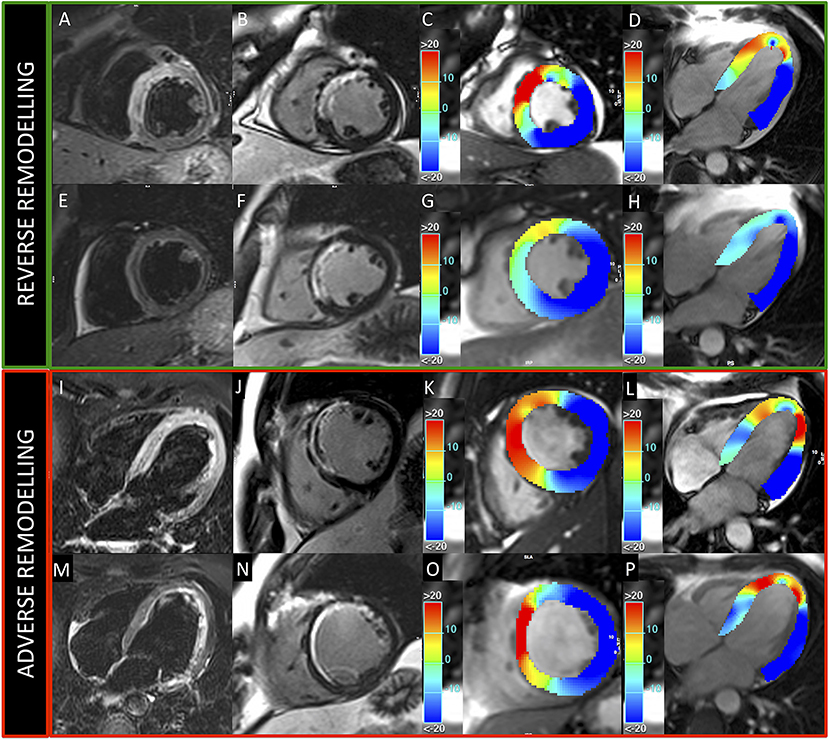

In this study, we categorized the population using the three LV remodeling patterns based on Bulluck's definition (7), observing a similar percentage distribution (adverse remodeling 49 vs. 45%, reverse remodeling 28 vs. 29%, and null remodeling 19 vs. 23%). For CMR parameters, the adverse remodeling group showed greater AAR, IS, and MVO at baseline CMR and greater IS at FU-CMR, as already reported (7). Otherwise, no differences in IS and MVO between reverse and null remodeling groups were found in our study. Notably, there were no differences in salvage myocardium extent among the three groups. Although IS and MVO are known predictors of adverse remodeling (7), the relationship between them and myocardial recovery is still an open issue (6, 7). Moreover, at FU-CMR, the adverse remodeling group showed lower LVEF, LV-RI, and greater IS, as compared to the other two groups. Regarding FT-CMR strain analysis, the adverse remodeling group showed worse GCS and GLS values at baseline and FU-CMR (Figure 5), if compared to reverse and null remodeling categories as one. Various studies investigated the value of FT-CMR features in predicting adverse remodeling (11, 12, 22), using different cut-off values and follow-up periods. For the definition of adverse LV remodeling, we considered LVEDV and/or an LVESV delta change of 12%, which is lower than most reports, and 6 months for follow-up, longer if compared to other studies, mostly around 3/4 months. Thus, this issue may have induced a larger rate of adverse remodeling in our population (49%), as compared to other cohorts (17–24.4%) (11, 12, 22, 23). In the majority of studies, baseline GLS was the best predictor of adverse remodeling among all strain values (11, 22–24). In particular, Reindl et al. (22) reported significant differences in baseline strain values and infarct size/MVO percentage between no remodeling and remodeling groups, as observed in our cohort. Moreover, they showed that a GLS-value > −14% was the best independent predictor of 4 months LV adverse remodeling (LVEDV delta change of 10%) with an AUC of 0.610, which do not differ substantially from our GLS AUC value of 0.639 using LVEDV/LVESV delta change of 12%. In the retrospective study of Cha et al. (11), at ROC curve analysis (AUC: 0.756, 95% CI = 0.636–0.887, p < 0.001), the GLS cut-off of −12.84% resulted in high sensitivity (Se: 85%) and low specificity (Sp: 61%) in predicting adverse remodeling at 6 months (LVEDV delta change of 20%), whereas in our study the optimal cut-off was lower (GLS > −10.21%), with lower sensitivity (Se: 35%) and higher specificity (Sp: 90%), likely reflecting the different criteria in classifying the remodeling groups. Interestingly, in our study GCS was the strongest predictor of adverse remodeling among the baseline strain values, as already reported by other authors (12, 25, 26). Holmes et al. (12) found that GCS was a superior predictor of LV adverse remodeling at 3 months follow-up than MVO, GLS, and GRS, although they considered a cohort of both STEMI and non-STEMI patients (12), differently from our population of STEMI only. Similarly, Buss et al. demonstrated that GCS is useful in predicting preserved LV function at 6 months follow-up but they did not evaluate LV remodeling groups (25).

Figure 5. Patients presenting reverse and adverse remodeling at baseline and follow-up CMRs. Images acquired in two patients with reverse (upper green panel) and adverse (lower red panel) remodeling, treated, respectively, with 500 and 250 mg ASA dose. Upper and lower rows represent exams acquired at baseline and 6-month follow-up, respectively. T2-weighted (A,E,I,M) and LGE (B,F,J,N) images show anterior myocardial infarction in both cases. GCS (C,G,K,O) and GLS (D,H,L,P) colored maps demonstrate better baseline values and higher recovery of myocardial contractility at follow-up in the patient with reverse remodeling.